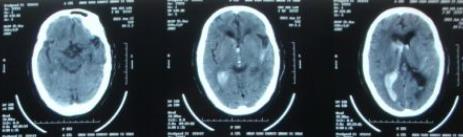

额顶叶脑梗死

查体:血压130/90 mmHg,神清。实验室检查:血、尿、便常规及肝肾功能等均正常。 头颅MR DWI可见右侧额顶叶高信号病灶。头颅CTA示右侧大脑中动脉管腔闭塞。

诊断:额顶叶脑梗死。 治疗:予阿司匹林抗血小板、阿托伐他汀调脂,以及依达拉奉清除氧自由基,以及维生素B1 和维生素B12 治疗。复方曲肽注射液改善患者凝血功能和微循环障碍,促进患者恢复。治疗3d后,患者言语不清及左侧肢体麻木症状明显缓解。